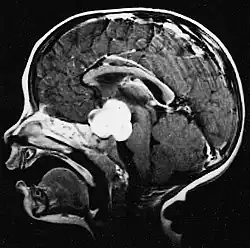

Na -MRI ukazuje intrakraniální tumor jako masivní lézi, která se po použití kontrastní látky může stát více luminiscenční. Vždy však dojde k anomálii signálu -Magnetická rezonance, která indikuje přítomnost neoplazie nebo vazogenního edému. Obvykle zvýšená luminiscence (zesílení kontrastu) svědčí pro nádor vyššího stupně malignity. Pro glioblastom je charakteristický kontrastní prstenec, jehož luminiscenční část odpovídá vitální části maligního nádoru a tmavší -hypointense oblast odpovídající nekróze tkáně.

Glioblastomy

Nejčastějšími a maligními nádory z gliových buněk jsou glioblastomy. Skládají se z heterogenní masy špatně diferencovaných buněk astrocytomu hlavně u dospělých. Obvykle se vyskytují v mozkových hemisférách, vzácněji v mozkovém kmeni nebo míše. Kromě velmi vzácných případů, jako všechny mozkové nádory, nepřesahují struktury centrálního nervového systému.

Glioblastom může vzniknout z difuzního (II. stupně) nebo anaplastický astrocytom (III. stupeň) rozvíjet. V druhém případě se nazývá sekundární. Pokud se však objeví bez předchozího zhoubného nádoru nebo důkazu o předchozím zhoubném bujení, označuje se jako primární. Glioblastomy se léčí chirurgicky, ozařováním a chemoterapií. Jsou obtížně léčitelné a jen málo případů přežívá déle než tři roky.